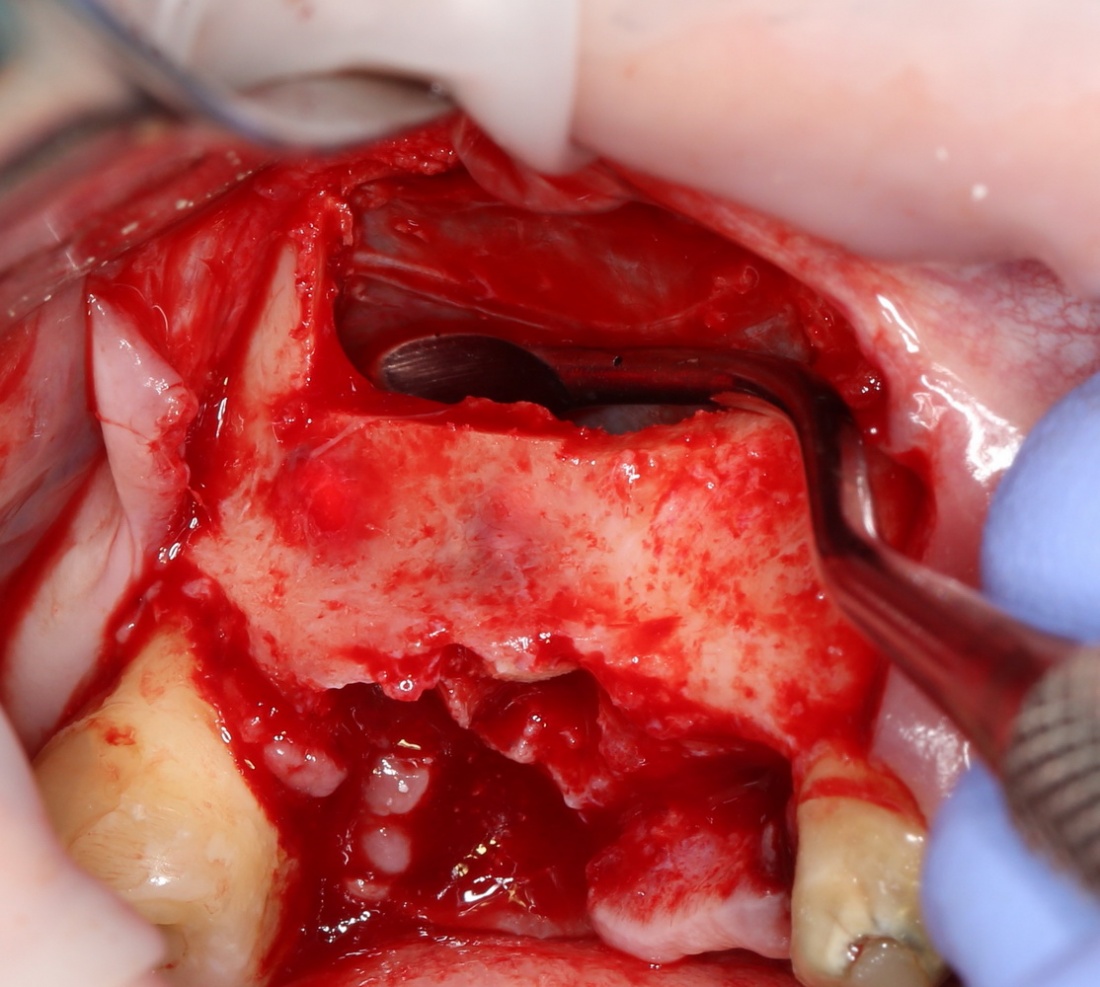

В данном случае я использовал Geistlich Mucograft Seal 8mm. Биоматериал в данном форм-факторе стоит дешевле, чем барьерная мембрана, а его диаметр позволяет легко перекрыть образовавшийся дефект слизистой:

Перед позиционированием Mucograft лучше намочить. Он станет более эластичным (без потери прочности) и мягким:

После чего, он легко приклеивается и перекрывает дефект:

Нам лишь остается заполнить образовавшееся субантральное пространство графтом (Bio-Oss) и закончить операцию синуслифтинга и остеопластики так, как мы планировали: